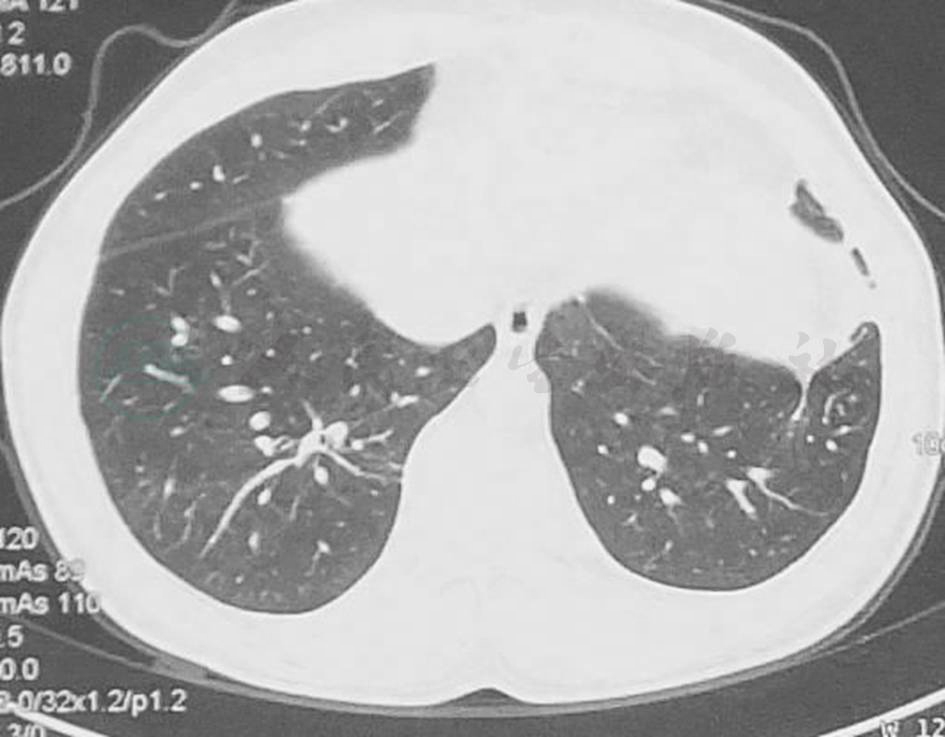

胸部CT示双肺多发结节、空洞影,左舌叶、右下叶大片渗出影(图1),一周后加重 (图2)。

图1 胸部CT表现(2011-8-10)

胸部CT显示双肺多发结节、空洞影,左舌叶、右下叶大片渗出影